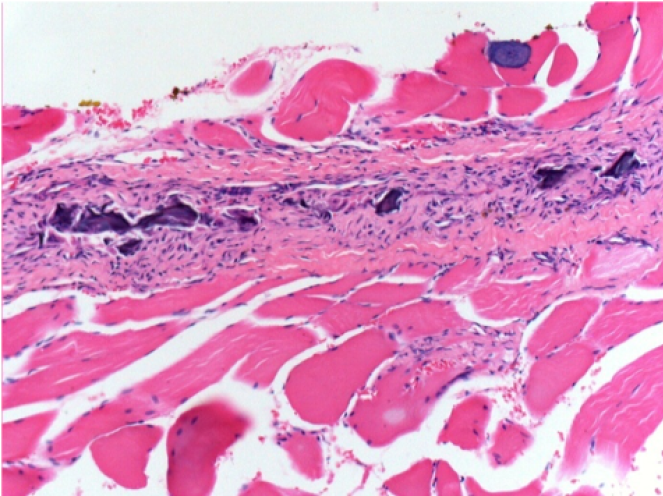

0,5 мл (5x 0,1 мл) підшкірна ін'єкція Ендопіл в праву підшкірну претибіальну ділянку.

Л:200x-Контроль-ПШ

П-10днів-ПШ-200X